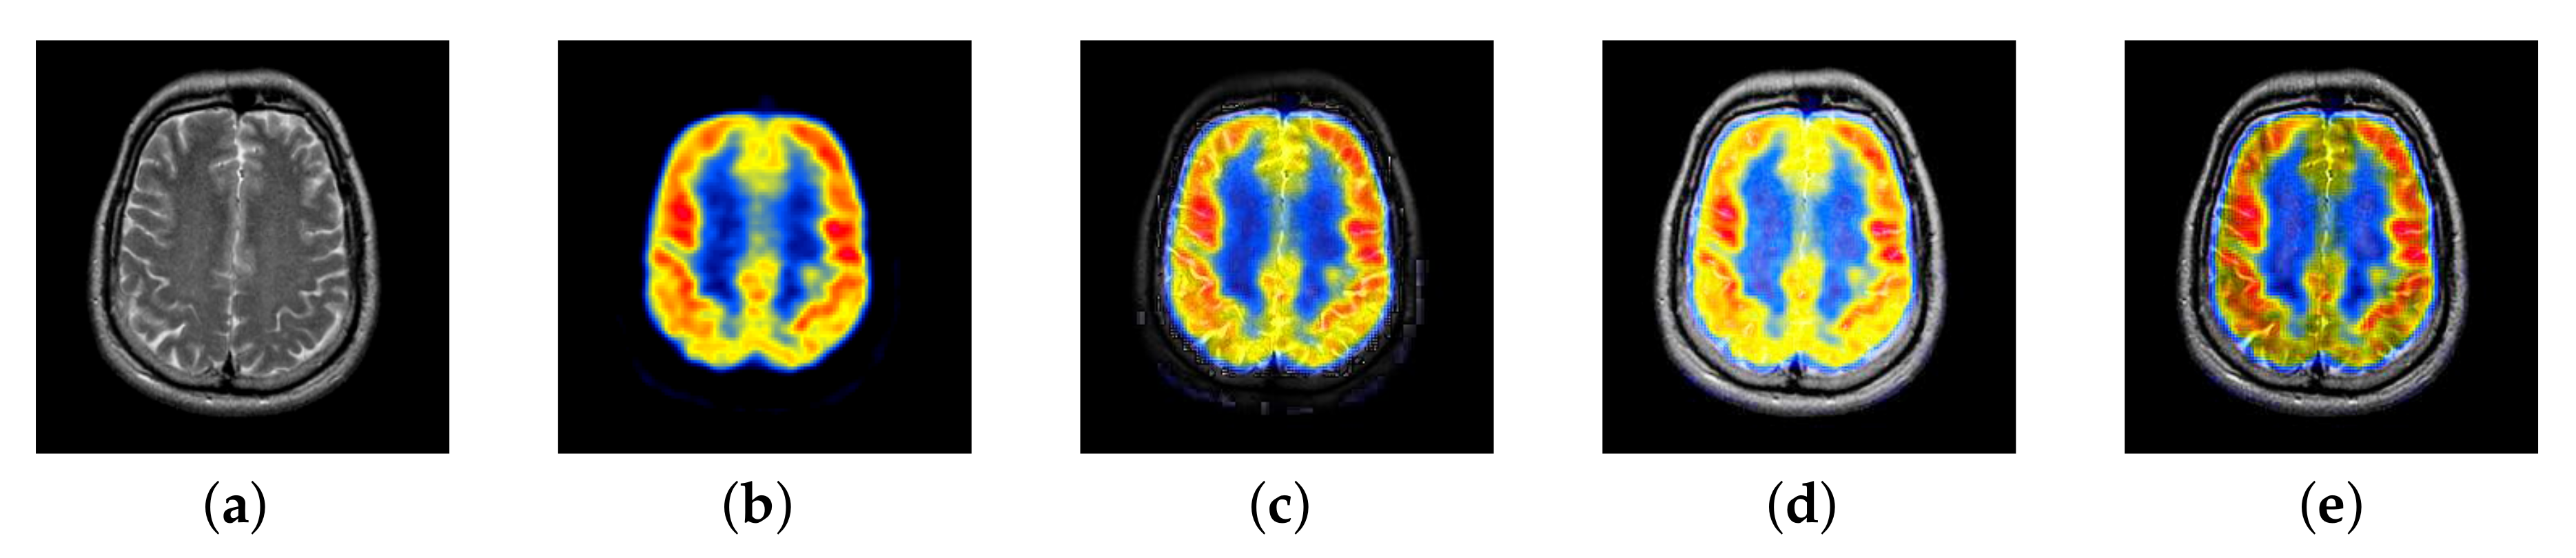

In previous intuitionistic fuzzy sets, scholars usually set to the order of 10 squares. Here, we set to 200, 300, 400, 500, 600, 700, and 800, respectively. Then, the image enhancement experiment is carried out, and the experimental results are shown in Figure 6. According to the results, we can find that, when is set to 500, the result is better than others.

Figure 6.

Source image and its image reconstructed by different algorithms): (a) Source image, (b) = 200, (c) = 300, (d) = 400, (e) = 500, (f) = 600, and (g) = 700, (h) = 800.